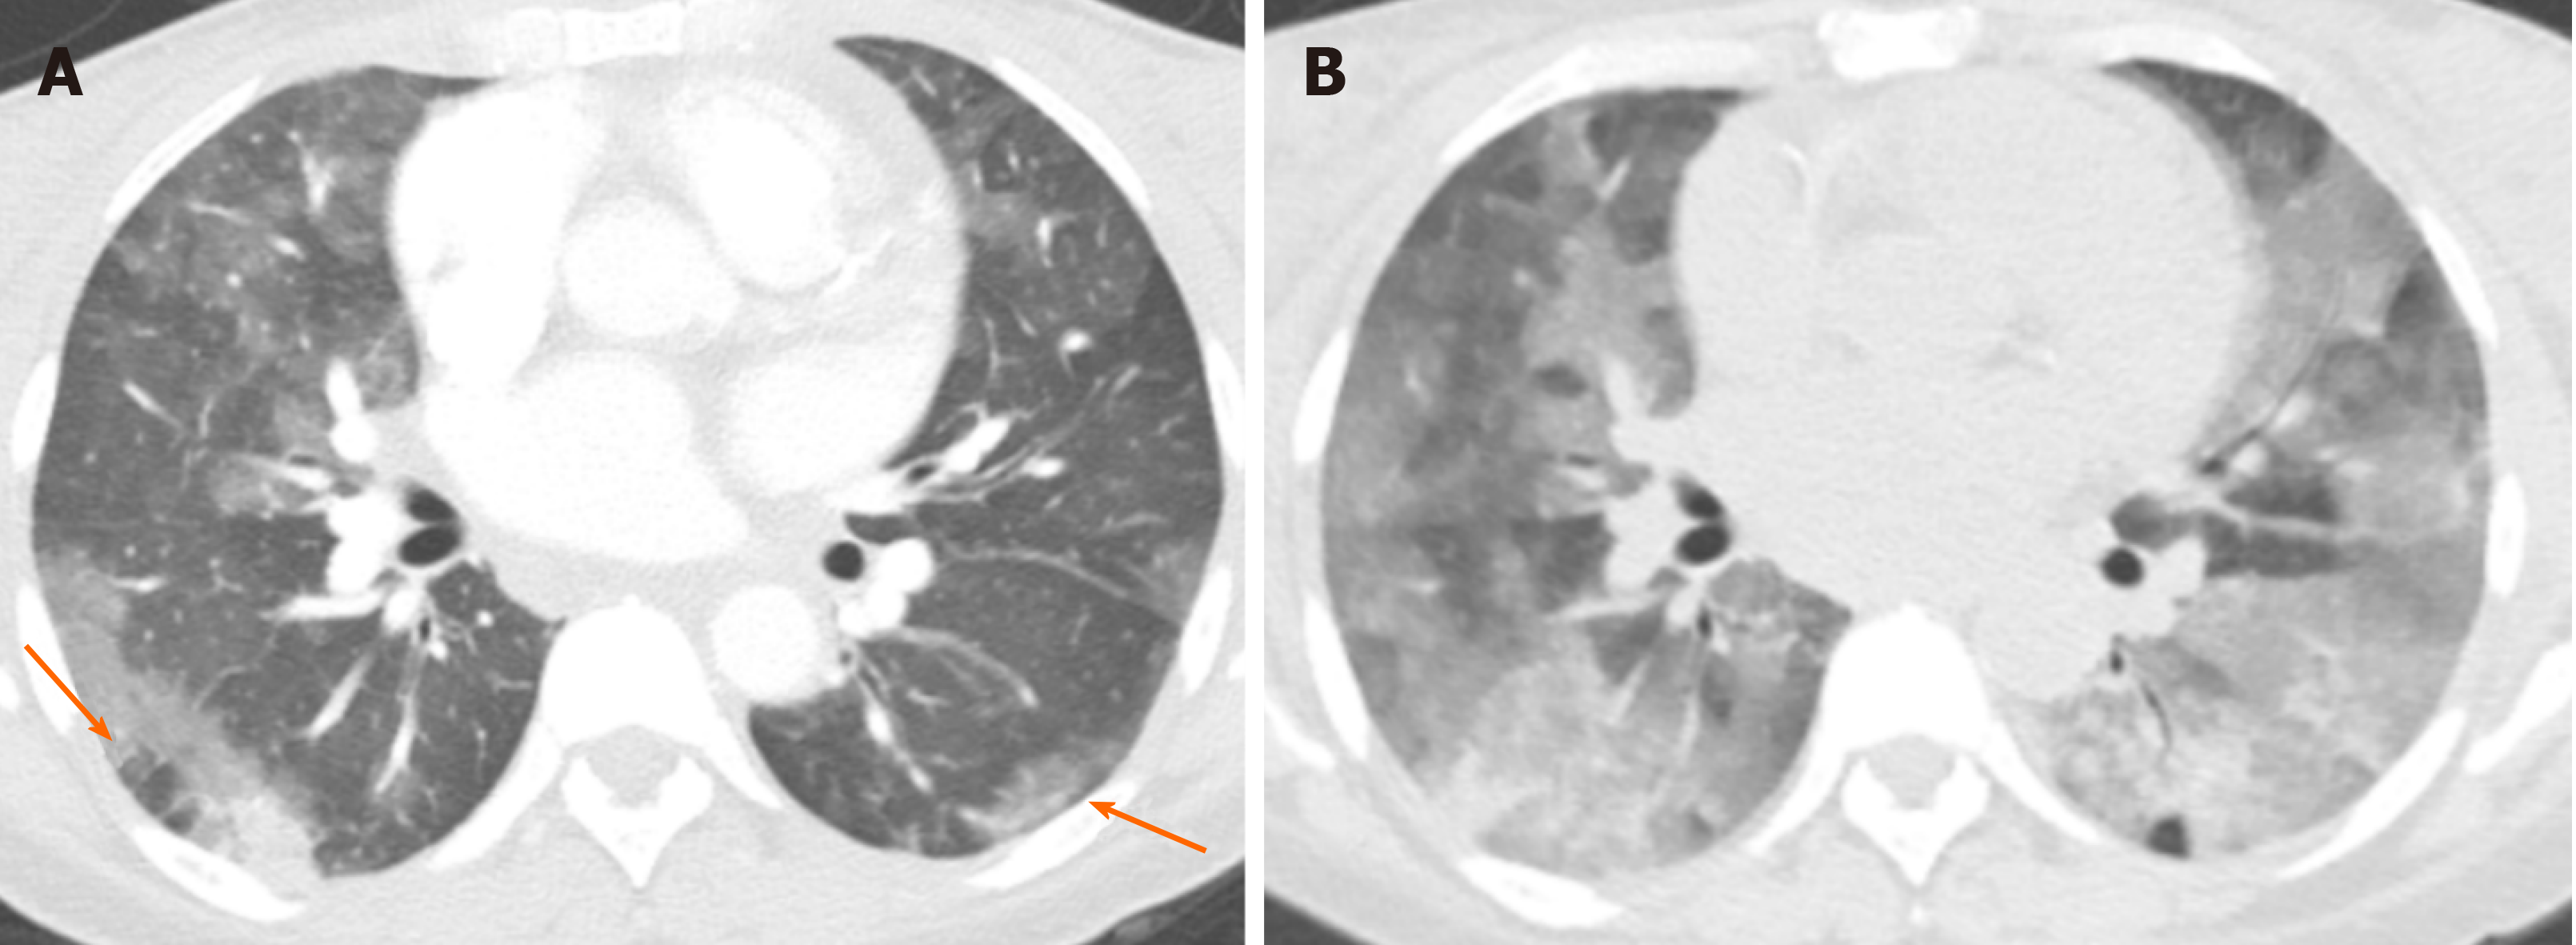

Интраренальная лоханка: рентгеновские снимки и примеры